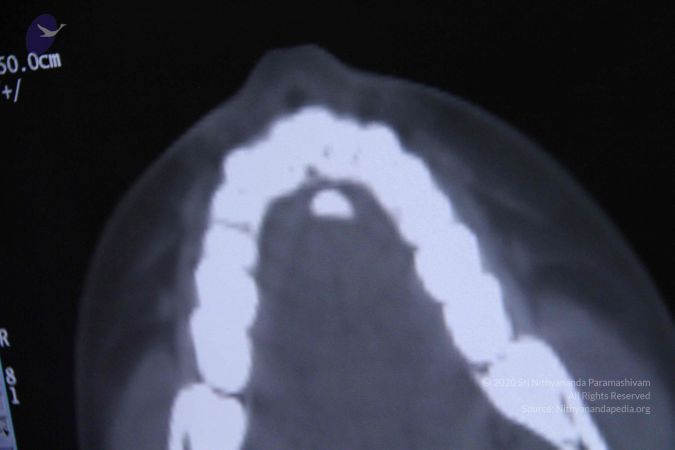

Scientific Validation of Materialization The most significant in a series of studies conducted by the research team were the tests done on Poornima (Ma Nithya Mahayogananda), a young entrepreneur and Paramahamsa Nithyananda’s energy channel from Singapore. On 6th September 2011, three different studies were conducted during a 4-hour session, in which Paramahamsa Nithyananda materialized a variety of objects through this individual, including sacred ash and precious stones. The studies were: 1) Whole body baseline CT scan of the subject Baseline whole-body CT scans proved the absence of any hidden objects in the body and vicinity of the subject. After the energy transfer from Paramahamsa Nithyananda to the subject, a repeat scan clearly shows the sudden appearance of a radio-opaque foreign body in the oral cavity without any delay or repositioning. The recording of the spiral CT after materialization revealed the presence of materialized objects both in sections and 3D format. 2) Simultaneous qEEG of Paramahamsa Nithyananda and the subject The qEEG recording of both Paramahamsa Nithyananda and the subject done during the process of energy transfer clearly showed ‘Entrainment’ (Synchronicity) in the brain waves of both individuals during the process of materialization, proving that a process of attunement was indeed taking place at the time

CT-SCAN-STUDIES-TO-DOCUMENT-POWER-OF-MATERIALISATIONIN-DEVOTEE-UNDER-CONTROLLED-CONDITIONS-PRE-AND-POST-INITIATION-BY-HDH